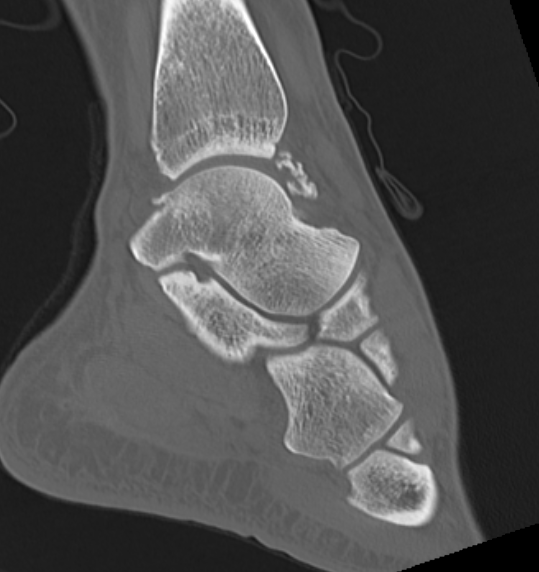

CT

Demonstrate osseous / calcified bodies